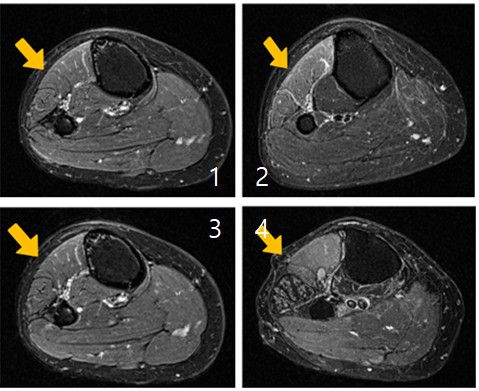

근육 손상이 진행되는 과정을 단계별로 보여주는 MRI 사진 |

무릎 부위 자기공명영상장치(MRI) 검사를 진행한 결과 무릎 외측을 지나는 비골신경이 섬유성 구조물에 의해 압박돼 있었다. 양 교수는 A씨 증상을 '비골신경병증에 의한 족하수'로 진단했다.

양 교수는 "뇌와 척추 MRI 검사에서 이상이 발견되지 않았는데도 발목이 들리지 않는다면 말초신경병증 가능성을 반드시 고려해야 한다"며 "비골신경병증은 무릎 부위 MRI만으로도 비교적 명확한 진단이 가능한 질환이지만 질환에 대한 인식이 부족하면 불필요한 검사와 치료로 시간을 허비하게 된다"고 말했다.

이 같은 치료로 증상 호전을 기대할 수 있지만 MRI 검사에서 비골신경 주행 부위의 압박이 명확하게 확인되거나 일정 기간 보존적 치료에도 불구하고 족하수 증상이 지속·악화하는 경우에는 수술적 치료를 고려한다.